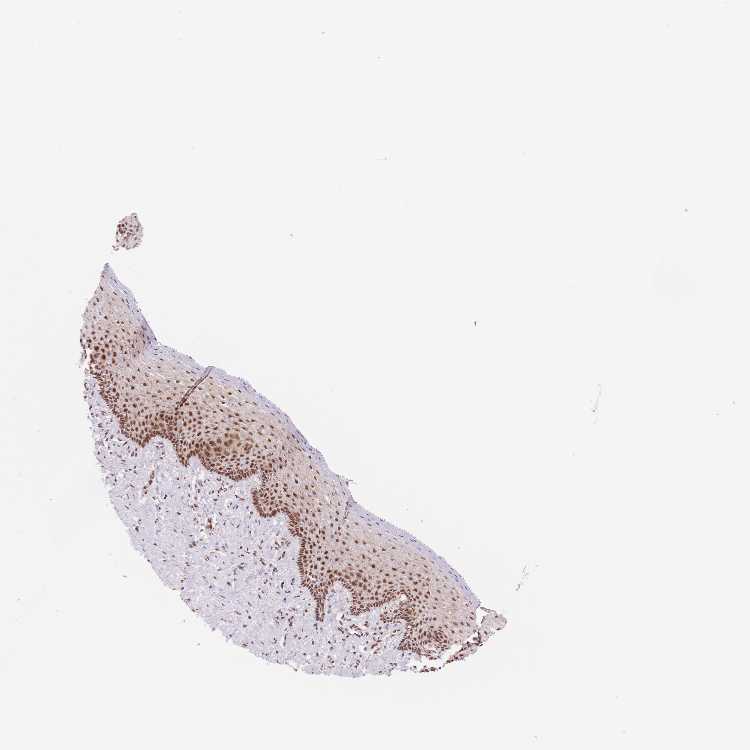

VAGINA - Antibody stainingi

Antibody staining in the annotated cell types in the current human tissue is reported as not detected, low, medium, or high, based on conventional immunohistochemistry profiling in selected tissues. This score is based on the combination of the staining intensity and fraction of stained cells.

Each image is clickable and will lead to virtual microscopy that enables deeper exploration of all samples and also displays staining intensity scores, fraction scores and subcellular localization as well as patient and tissue information for each sample.

Antibody HPA061803Antibody HPA062802Antibody CAB046022

Squamous epithelial cells HighLowMedium